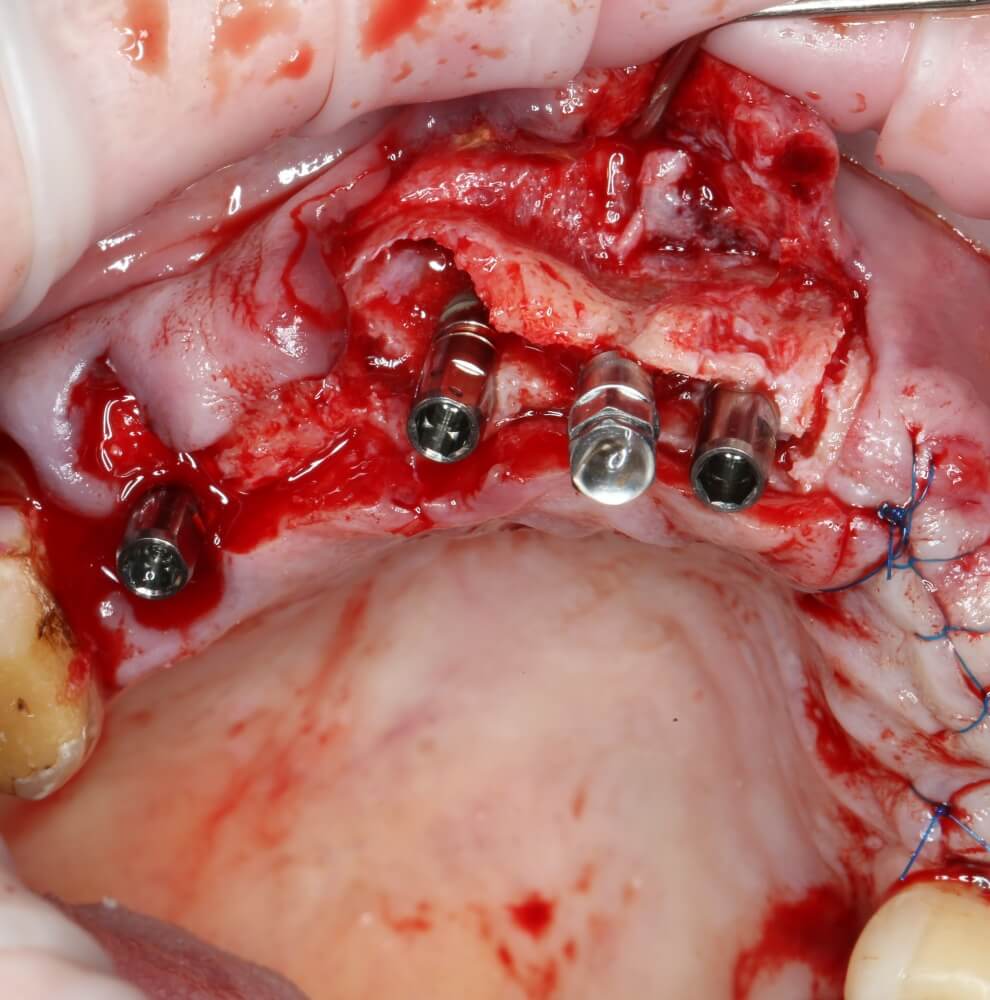

Глянем на то, что получилось:

Осталось адаптировать костный блок (убрать острые края), проверить его фиксацию и, при необходимости, добавить винты. Десятисекундное дело.